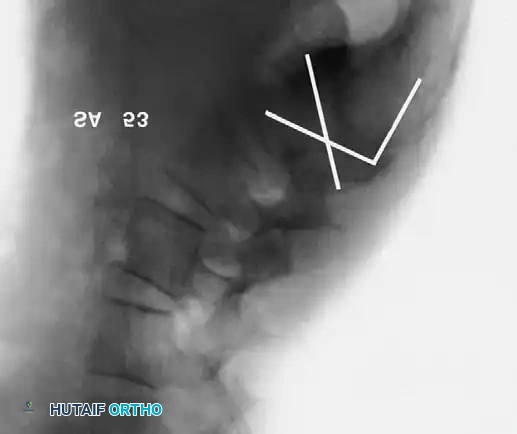

Boxall's Slip Angle:

Boxall et al. established that angular relationships (sagittal rotation or slip angle) are superior predictors of instability and progression compared to simple translational percentage. A high slip angle indicates severe localized lumbosacral kyphosis.